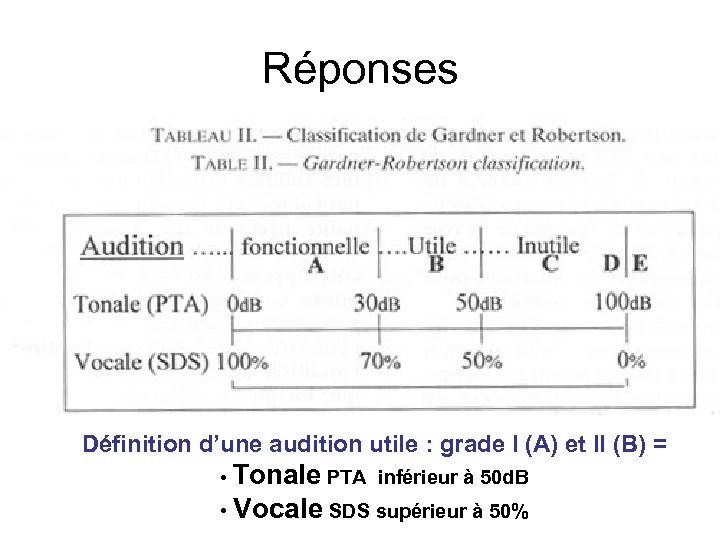

Réponses Définition d’une audition utile : grade I (A) et II (B) = • Tonale PTA inférieur à 50 d. B • Vocale SDS supérieur à 50%

Réponses Définition d’une audition utile : grade I (A) et II (B) = • Tonale PTA inférieur à 50 d. B • Vocale SDS supérieur à 50%